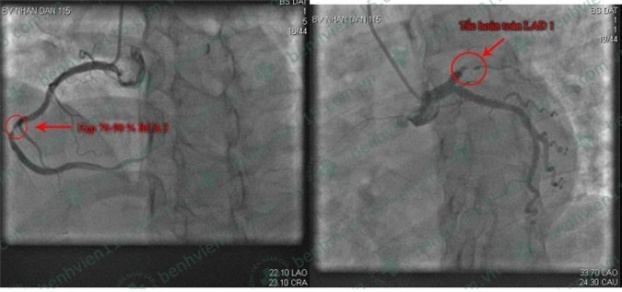

| Hình ảnh chụp mạch vành của bệnh nhân. Ảnh: BVCC |

Tại đây, các bác sĩ chẩn đoán chị V. bị nhồi máu cơ tim cấp sau chấn thương ngực kín. Các bác sĩ nhanh chóng chụp mạch vành cấp cứu và can thiệp mạch vành. Hiện sức khỏe bệnh nhân đã ổn định.

Mặc dù bệnh nhân còn rất trẻ, yếu tố nguy cơ tim mạch trước đó không ghi nhận, kết quả khảo sát mạch vành vẫn có sang thương nặng, rộng, đa mạch máu, khả năng do bệnh lý xơ vữa cao.